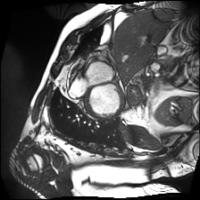

In our semi-supervised segmentation model, the CycleGAN is instead used to map images to their corresponding segmentation mask and vice-versa. The first generator (), corresponding to the segmentation network that we want to obtain, learns a mapping from an image to its segmentation labels. The first discriminator () tries to differentiate these generated labels from real segmentation masks. Note that the combination of of is similar to semi-supervised segmentation approach presented in [31]. Conversely, the second generator () learns to map a segmentation mask to its image. In our semi-supervised segmentation setting, this generator is only used to improve training. Likewise, the second discriminator () receives an image as input and predicts whether this image is real or generated. To enforce cycle consistency, generators are trained so that feeding the labels generated by for an image into gives that same image, and passing back to the image generated by for a segmentation mask gives that same mask. Figure 2 shows examples of images, ground truth labels, generated images and generated labels obtained for the three datasets used in our experiments.

![]() |

| Image | Ground truth labels | Generated image | Generated labels |